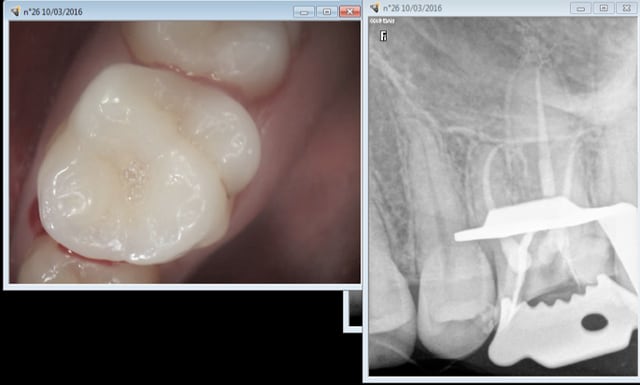

10/03/2016 à 16h08

Ca c'est quand meme plus classe pour le meme tarif ! -)

Oh le vilain il m'a dévitalisé une dent saine ! je suis à la CMU c'est une honte de profiter des plus démunis, cochon de dentiste ! -)

Capture d e cran 2016 03 10 15.07 - Eugenol